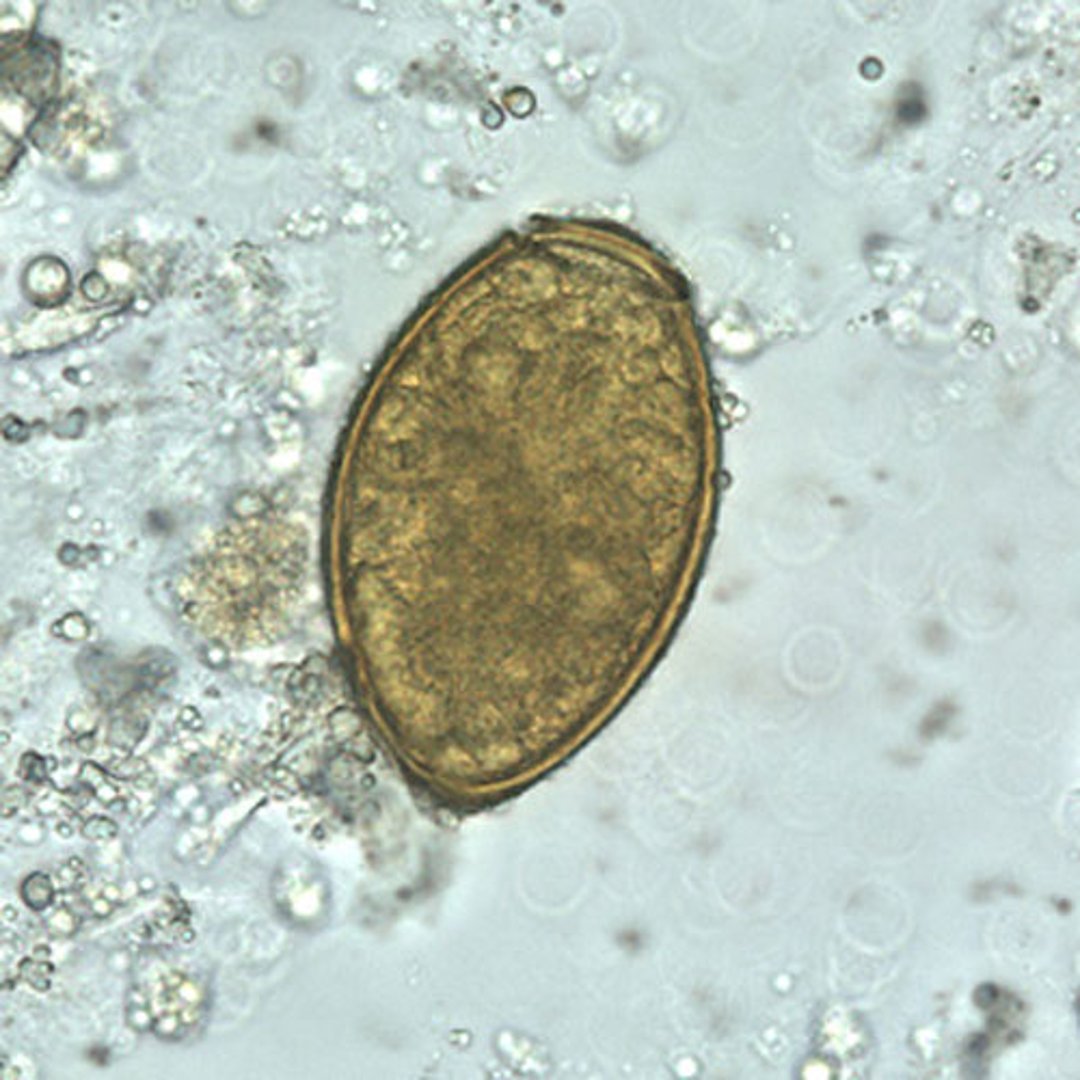

Huevo de Paragonimus westermani

Los huevos de P. westermani varían de 80 a 120 micrómetros de largo por 45 a 70 micrómetros de ancho. Son de color marrón amarillento, ovoides o alargados, y tienen una cáscara gruesa. Los huevos son a menudo asimétricos con un extremo ligeramente aplanado. En el extremo grande, el opérculo es claramente visible. El extremo abopercular está engrosado.

Los huevos no están embrionados cuando salen a través del esputo o las heces.